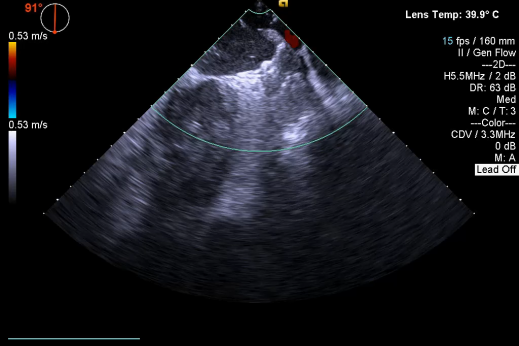

▲开释后,DSA与TEE观察均无残存分流

其中首场公开演示的左心耳血栓封堵病例拥有极高难度,患者术前TEE显示左心耳血栓形成伴机化,血栓位于心耳中段,近中端絮状物显著。封堵机遇只有一次,选型和操作稍有失误,城市增长手术风险。因而手术采取全麻,并装置了抗栓塞脑动脉;ぷ爸,以削减术中风险。通过TEE疏导下丈量左心耳大幼以及确认左心耳血栓地位,李岳春教授凭借自身丰硕经验最终决定使用LAmbre 2632型号,选取推送式植入法将左心耳血栓牢牢锁死于远端,并且封堵器一次成型,封堵成效极佳,实现后取出脑;ぷ爸,均未见血栓,顺利实现了此台高难度的手术,获得了学员们的一致认可。